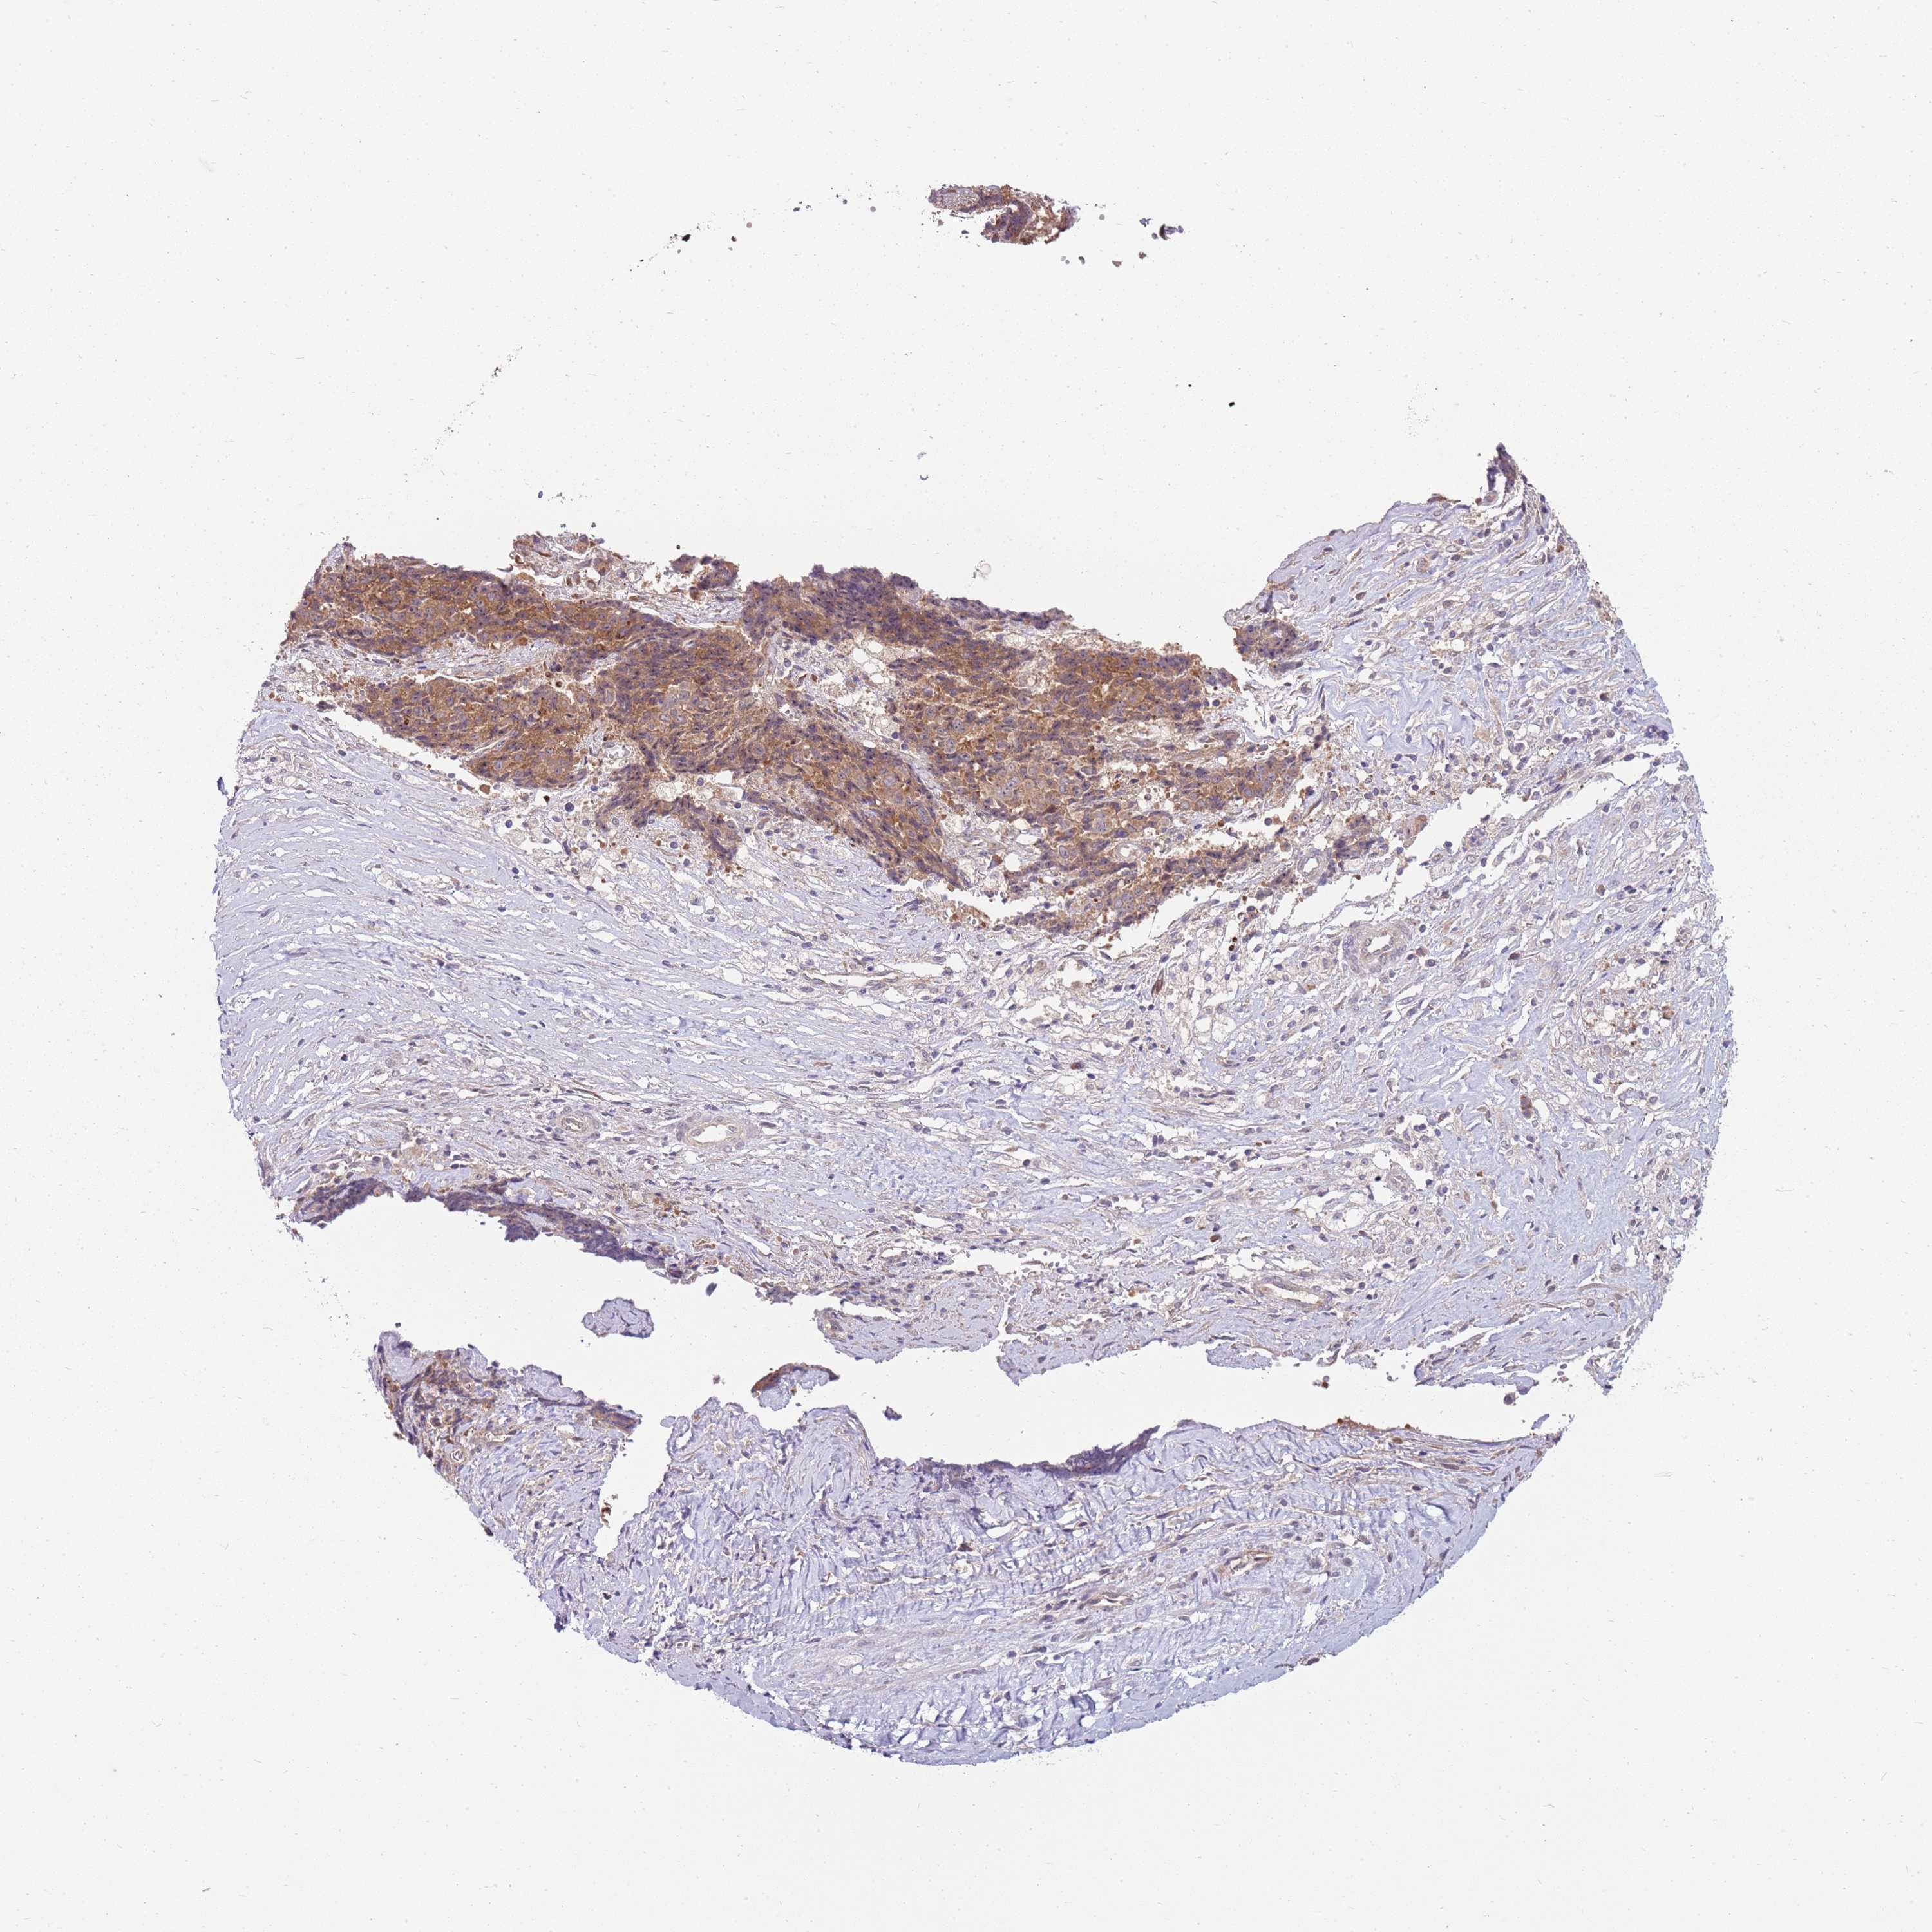

OVARIAN CANCER - Protein expressioni

A mouse-over function shows sample information and annotation data. Click on an image to view it in a full screen mode. Samples can be filtered based on level of antibody staining by selecting one or several of the following categories: high, medium, low and not detected. The assay and annotation is described here.

Note that samples used for immunohistochemistry by the Human Protein Atlas do not correspond to samples in the TCGA dataset.

Antibody stainingi

Antibody staining in the annotated cell types in the current human tissue is reported as not detected, low, medium, or high, based on conventional immunohistochemistry profiling in selected tissues. This score is based on the combination of the staining intensity and fraction of stained cells.

Each image is clickable and will lead to virtual microscopy that enables deeper exploration of all samples and also displays staining intensity scores, fraction scores and subcellular localization as well as patient and tissue information for each sample.

Antibody HPA047624

Antibody HPA054627

Staining

High

Medium

Low

Not detected

Intensity

Strong

Moderate

Weak

Negative

Quantity

>75%

75%-25%

<25%

None

Location

Nuclear

Cytoplasmic/membranous

Cytoplasmic/membranous,nuclear

Cystadenocarcinoma, serous, NOS

Carcinoma, NOS

Cystadenocarcinoma, mucinous, NOS

Carcinoma, endometroid